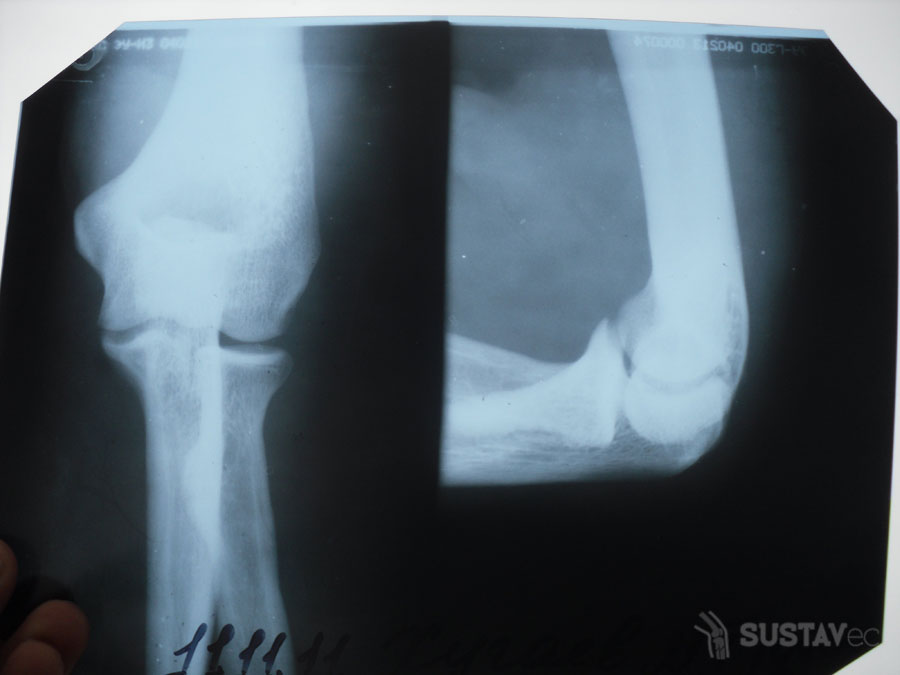

- Рентгеновский снимок, чтобы исключить патологию сердечной мышцы, позвоночника и локтевого сустава.